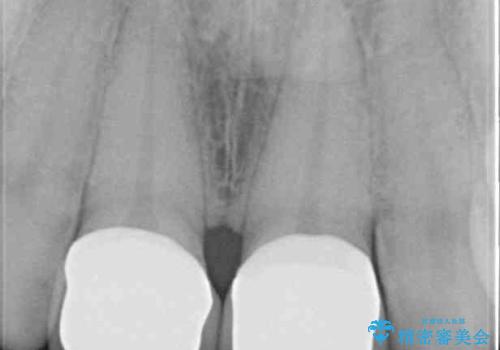

- 上の前歯2本の審美障害を気にして来院された患者様です。樹脂が無造作に充填されており、色合いも形態も不自然で、歯肉も腫れているため、オールセラミッククラウンにて補綴することとしました。

充填されたレジンを取り除いたところ、歯肉の炎症による出血が認められました。セラミッククラウン装着後は歯肉が腫れることもなく、仕上がりも自然な歯のようになり、患者様には大変満足していただきました。